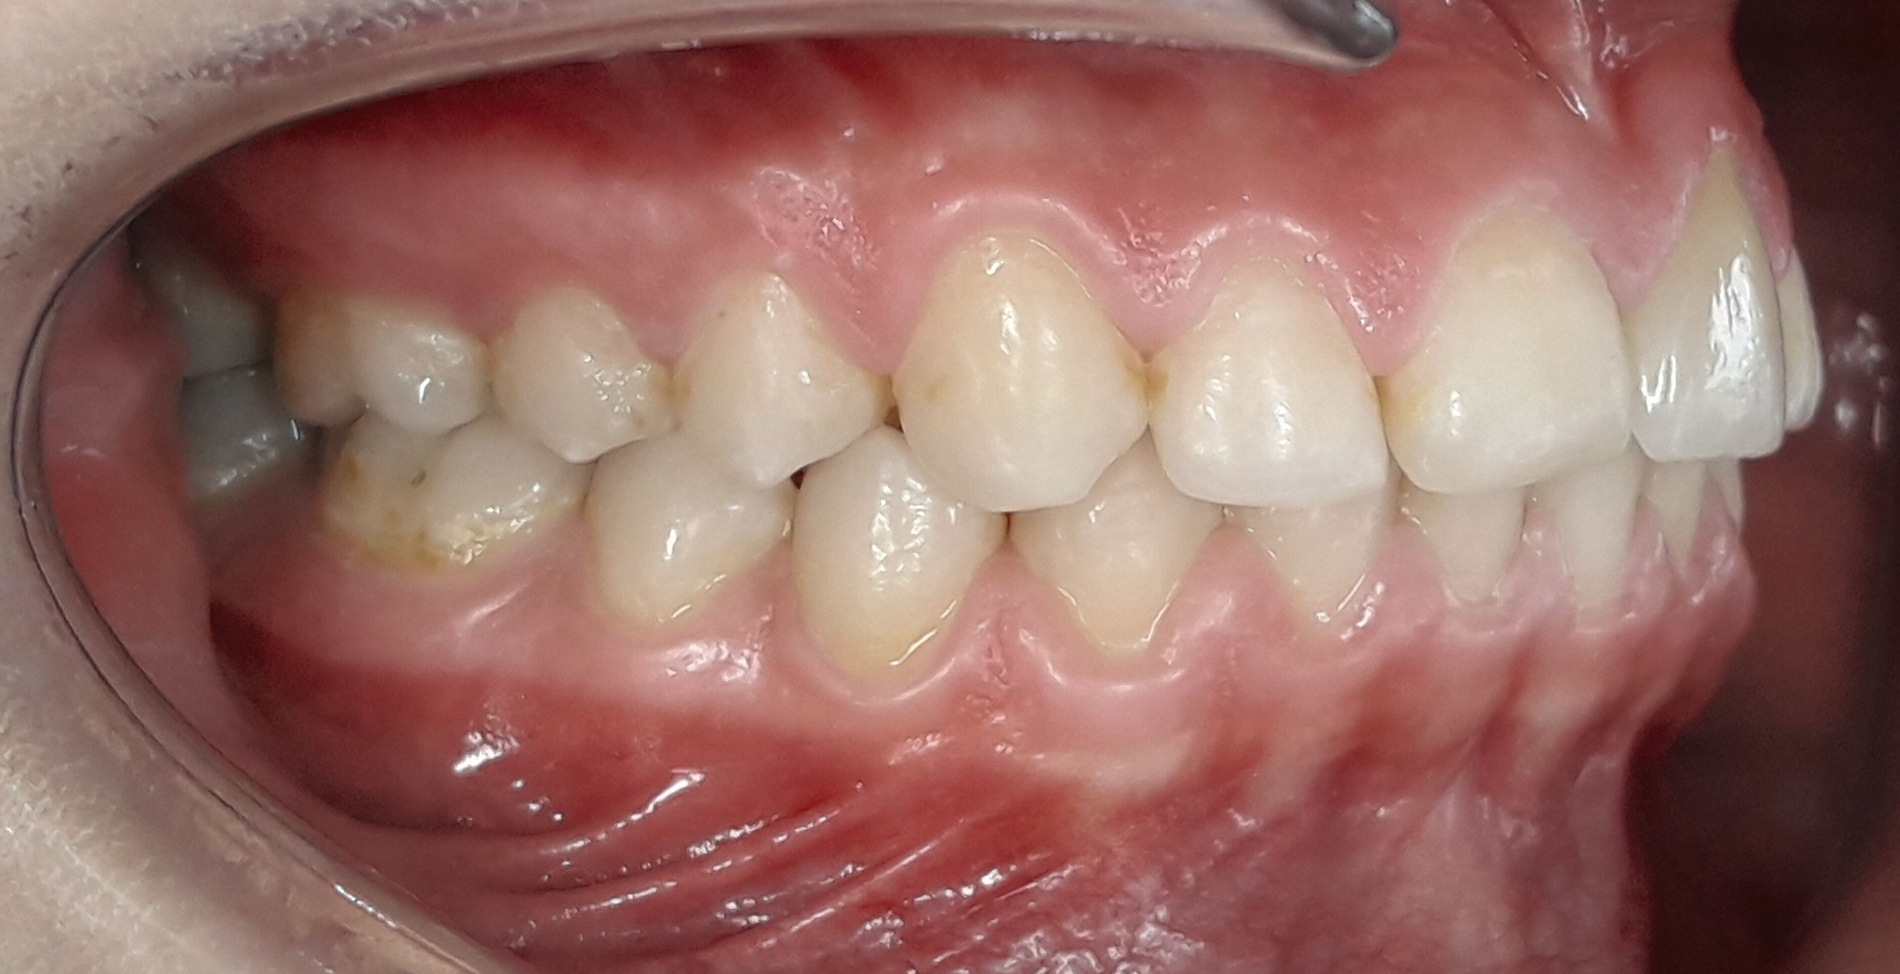

Im Februar 2019 wurde die kieferorthopädische Klinik von der Erstautorin übernommen. Bei der Auswertung der vorgefundenen Daten der Patientin wurde festgestellt, dass der linke obere zentrale Schneidezahn vor sechs Monaten extrahiert worden war. Die festsitzende Apparatur war im Oberkiefer bereits eingegliedert. Die Druckfeder zwischen Zahn 11 und 22 diente zur Lückenöffnung für den späteren prothetischen Ersatz des Zahnes 21. Auch auf den persistierenden linken Milcheckzahn war ein Bracket geklebt. Die Okklusion im Bereich der ersten Molaren war rechts und links neutral (Abbildung 2).